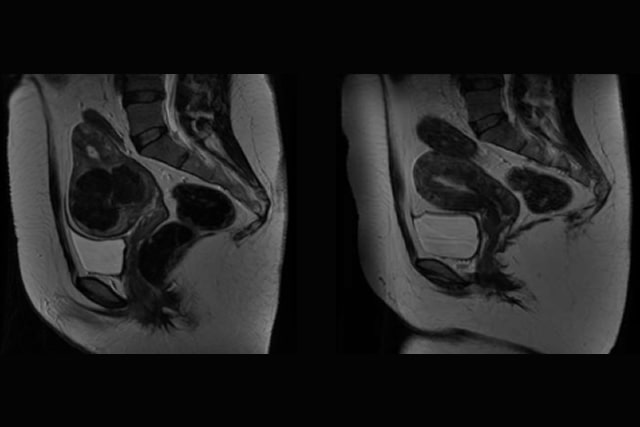

Ecografia Ginecológica Doppler 3D

Permite-nos ver o útero com uma definição quase real.

Ecografia Doppler 3D - Elastografia para avaliação de miomas, duas novidades no tratamento de miomas.